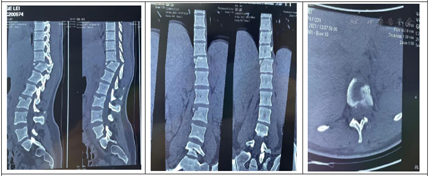

胸椎CT示:胸12椎体骨折伴脱位,相应水平椎管内骨块占位,伴局部后凸畸形。胸椎MRI示:胸12椎体骨折脱位,相应水平硬膜囊及脊髓受压,并脊髓损伤。

西医诊断依据:(1)主诉:坠落伤致双下肢感觉功能障碍1周余。(2)专科检查:抬入病房,被动体位。腰背部可见原手术切口,愈合良好,未见明显红肿及渗出。感觉系统:双下肢感觉大致正常,肛周感觉减退。双下肢体关节位置觉、运动觉存在。运动系统:双侧肢体未见肌肉萎缩。双侧肢体肌张力不高。肌力:左侧:髂腰肌肌力Ⅲ级,股四头肌肌力Ⅲ-级,胫前肌肌力Ⅲ-级,足拇背伸肌肌力级Ⅲ-,趾屈肌肌力Ⅲ-级;右侧:髂腰肌肌力Ⅲ级,股四头肌肌力Ⅲ级,胫前肌肌力Ⅲ级,足拇背伸肌肌力级Ⅲ,趾屈肌肌力Ⅲ级;浅反射:上、中、下腹壁反射正常,肛门反射减弱。深反射:双侧膝腱反射、跟腱反射减弱。病理征:双侧Hoffman征(-),Rossolimo征(-),Babinski征(-),双侧髌阵挛、踝阵挛(-)。骶残留:肛周针刺觉减弱,肛门深压觉减弱,肛门括约肌松弛,自主收缩存在。不可以独自坐立,不能独自站立。洗漱、穿衣、进食等ADL完全依赖。(3)辅助检查:胸腰椎CT(2021年4月29日外院)胸12椎体骨折伴脱位,相应水平椎管内骨块占位,伴局部后凸畸形。胸椎、腰椎、颈椎MRI提示:①胸12椎体骨折脱位,相应水平硬膜囊及脊髓受压,并脊髓损伤;②腰3椎体骨折,胸12附件区软组织肿胀,结合西安市红会医院CT检查胸12附件骨折;③腰5-骶1椎间盘变性、突出,同水平硬膜囊受压;④胸腰骶部软组织水肿;⑤颈椎生理曲度变直,颈3~4、颈4~5、颈5~6椎间盘变性、突出,相应水平硬膜囊受压。